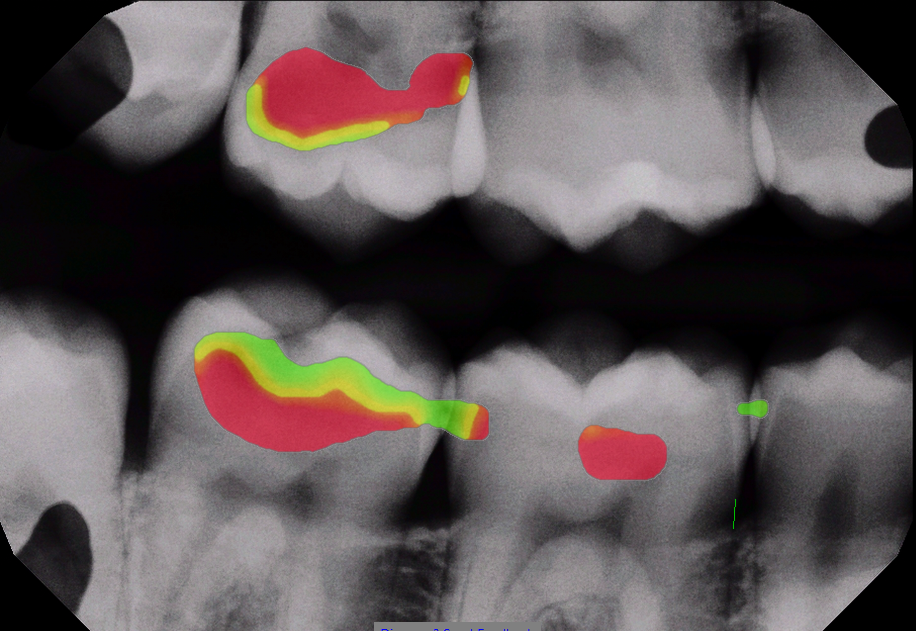

Original bitewing With AI overlay

Green/yellow/red color display has not received FDA clearance.